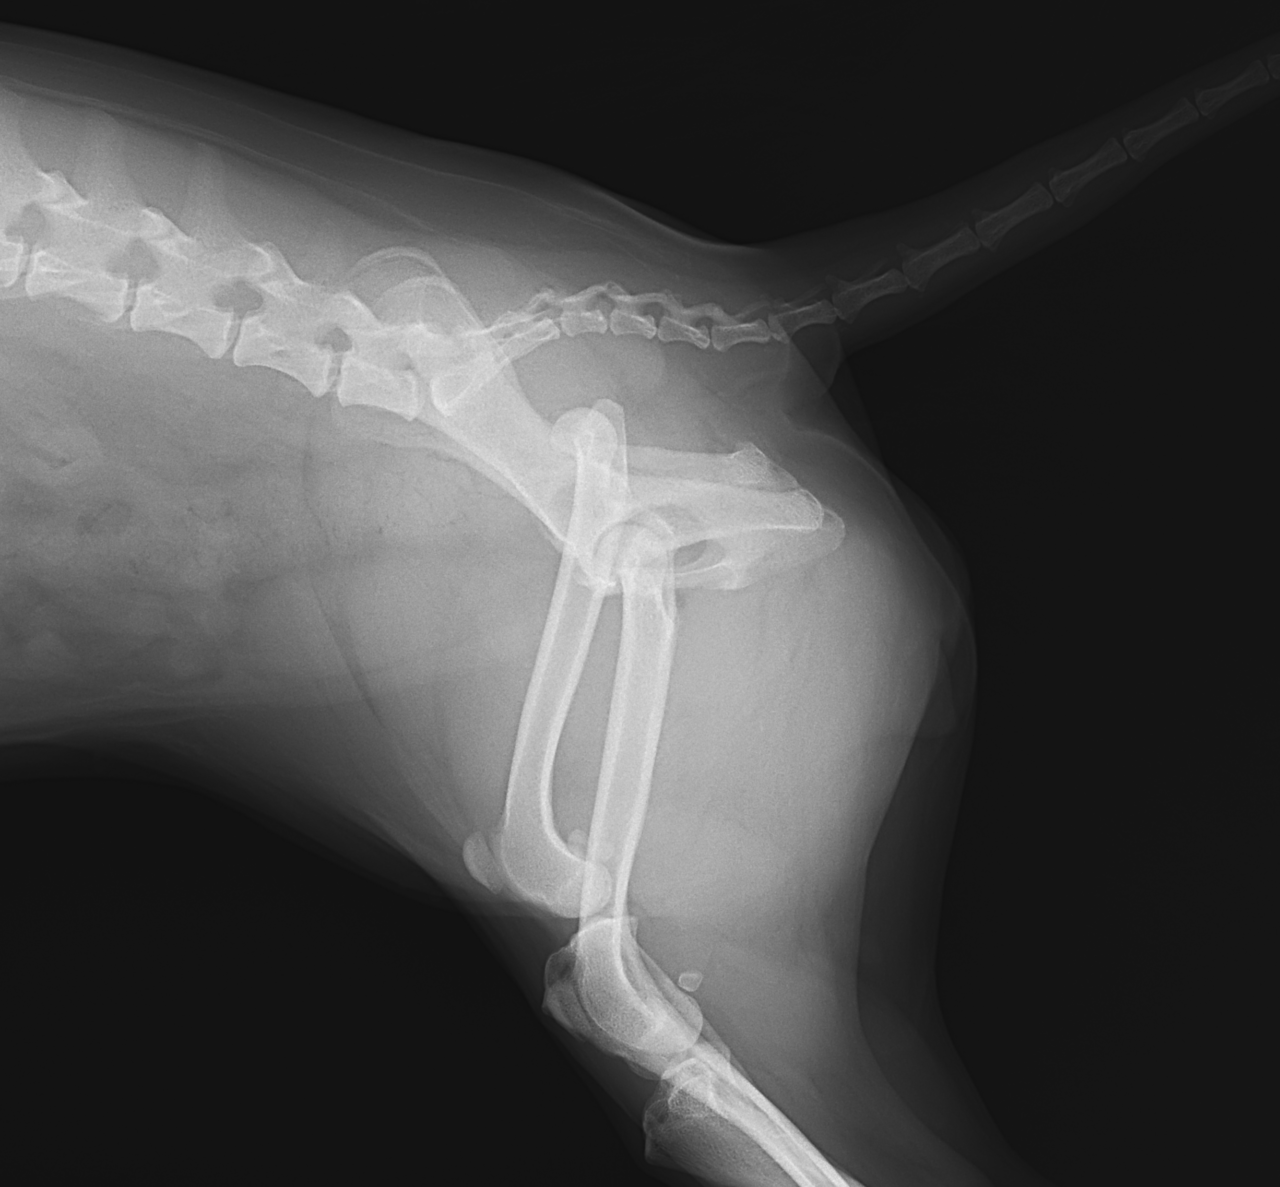

輪禍外傷による股関節脱臼の患者さんに対してBullet–Shaped Toggle Rod (BUSTOR)で整復を行いました。本症例は恥骨の骨折も併発していたため、CTで寛骨臼の評価も実施しました。低侵襲かつ短時間で整復が可能です。しばらくは安静が必要です。